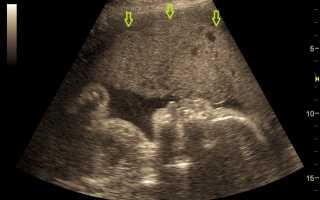

Отклонения в развитии плода обычно выявляют во время планового ультразвукового исследования, проводимого во втором триместре беременности, начиная с 20-й недели.

- Трансабдоминальное УЗИ матки. Исследование проводится не ранее 18-й недели беременности. Оно помогает выявить аномальное разрастание плацентарной ткани и сравнить его с нормальными показателями для данного срока. УЗИ позволяет обнаружить структурные изменения в тканях плаценты, серьезные внутриутробные аномалии развития плода, а также признаки гипотрофии и многоводия.